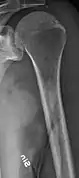

The diagnostic examination of a person with suspected multiple myeloma typically includes a skeletal survey. This is a series of X-rays of the skull, axial skeleton, and proximal long bones. Myeloma activity sometimes appears as "lytic lesions" (with local disappearance of normal bone due to resorption) or as "punched-out lesions" on the skull X-ray ("raindrop skull"). Lesions may also be sclerotic, which is seen as radiodense.[70] Overall, the radiodensity of myeloma is between −30 and 120 Hounsfield units (HU).[71] Magnetic resonance imaging is more sensitive than simple X-rays in the detection of lytic lesions, and may supersede a skeletal survey, especially when vertebral disease is suspected. Occasionally, a CT scan is performed to measure the size of soft-tissue plasmacytomas. Bone scans are typically not of any additional value in the workup of people with myeloma (no new bone formation; lytic lesions not well visualized on bone scan).

Humerus with multiple myeloma lesions

Same humerus before, with just subtle lesions